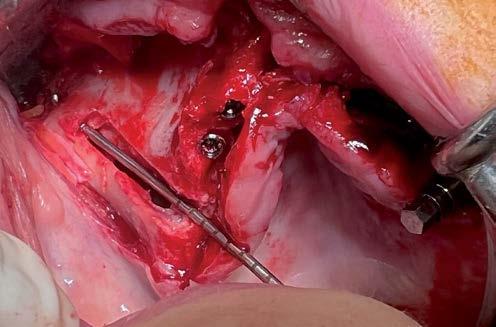

Elevación de seno transcrestal con implantes cortos versus elevación de seno convencional con ventana lateral

Estudio retrospectivo comparativo a boca partida

Aún así, existen hoy en día situaciones en las que la inserción de un implante corto o extra-corto no es posible de forma directa, cuando existe un volumen óseo residual por debajo de los 5 mm, existiendo en estos casos una nueva alternativa terapéutica a la elevación de seno convencional que es la elevación de seno transcrestal (14-15).

En esta técnica se accede a través de la cresta mediante la confección de un neoalveolo generado por fresado al seno maxilar despegándose la membrana desde este neoalveolo e insertándose el implante corto o extra-corto con o sin injerto asociado (en función del volumen en altura que se pretende ganar) (14-15).

MATERIAL Y MÉTODO

Fueron reclutados de forma retrospectiva pacientes en los que se hubiesen realizado ambas

técnicas de abordaje de seno maxilar: elevación convencional o la inserción de implantes cortos y extra-cortos mediante elevación transcrestal, desde enero de 2010 en adelante. Todos los pacientes fueron estudiados antes de la inserción de los implantes mediante modelos diagnósticos, exploración intraoral y realización de un TAC dental (Conebeam) analizado posteriormente mediante un software específico (BTI-Scan II).

Antes de la inserción de los implantes se utilizó una premedicación antibiótica consistente en amoxicilina 2 gr vía oral una hora antes de la intervención y paracetamol 1 gramo vía oral (como analgésico). Posteriormente, los pacientes prosiguieron con un tratamiento de amoxicilina 500-750 mg vía oral cada 8 horas (según peso) durante 5 días.

Los implantes y la elevación de seno por abordaje lateral fueron colocados por un mismo cirujano. La ventana de acceso lateral se realizó, en todos los casos, con el